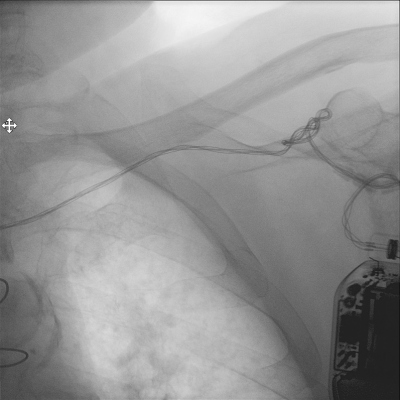

Po třech letech od implantace ICD byl na pravidelné kontrole přístroje v ambulanci zjištěn pokles vlny R na 4 mV a výrazný skokový nárůst impedance defibrilační elektrody na 2 300 ohmů. Dále byla zjištěna porucha stimulačních funkcí, kdy i při maximálním výdeji přístroje nebyla přítomna elektrická odpověď myokardu. V paměti přístroje nebyl žádný záznam o arytmiích.Pacientka popírala případný úraz nebo manipulaci s přístrojem v podkožní kapse a byla přijata k revizi systémuICD. Dle peroperačníhortgbylo patrné mnohočetné protočení elektrody mezi generátorem a vstupem do žilního systému (obr. 2), což se potvrdilo při následném otevření kapsy ICD (obr. 3).Následně byl proveden opatrný pokus o uvolnění původní elektrody, která ale byla pevně přirostlá k podkladu v celém jejím průběhu. Proto byla pouze zaslepena a fixována ke spodině kapsy ICD. Pro časový odstup od implantace ICD (tři roky) a rizikovost případné extrakce defibrilační elektrody u polymorbidnípacientky jsme neindikovali extrakci původní elektrody. Po ověření průchodnosti podklíčkové žíly flebografií byla pacientce Seldingerovou punkční metodou cestou podklíčkové žíly implantována nová defibrilační elektroda Durata 7122Q (St. JudeMedical, USA) do hrotu pravé komory. Parametry elektrody byly optimální: stimulační práh 1,1 V, senzing vlny R 12 mV, odpor defibrilační elektrody 580 ohmů, defibrilační odpor 87 ohmů. Na novou elektrodu byl napojen přístroj FortifyAssura VR (St. JudeMedical, USA). Druhý den byl proveden rtg snímek hrudníku v předozadní a boční projekci, dle kterého byla elektroda ve vyhovující pozici.Funkce systému před propuštěním byla také správná (senzing vlny R 12 mV, stimulační práh 0,75 V, odpor elektrody 550 ohmů a defibrilační odpor 56 ohmů). Pacientka byla propuštěna do domácí péče s dalším ambulantním sledováním, kdy dosud neměla arytmické události nebo komplikace systémuICD (v době psaní článku šest měsíců od revize systému).